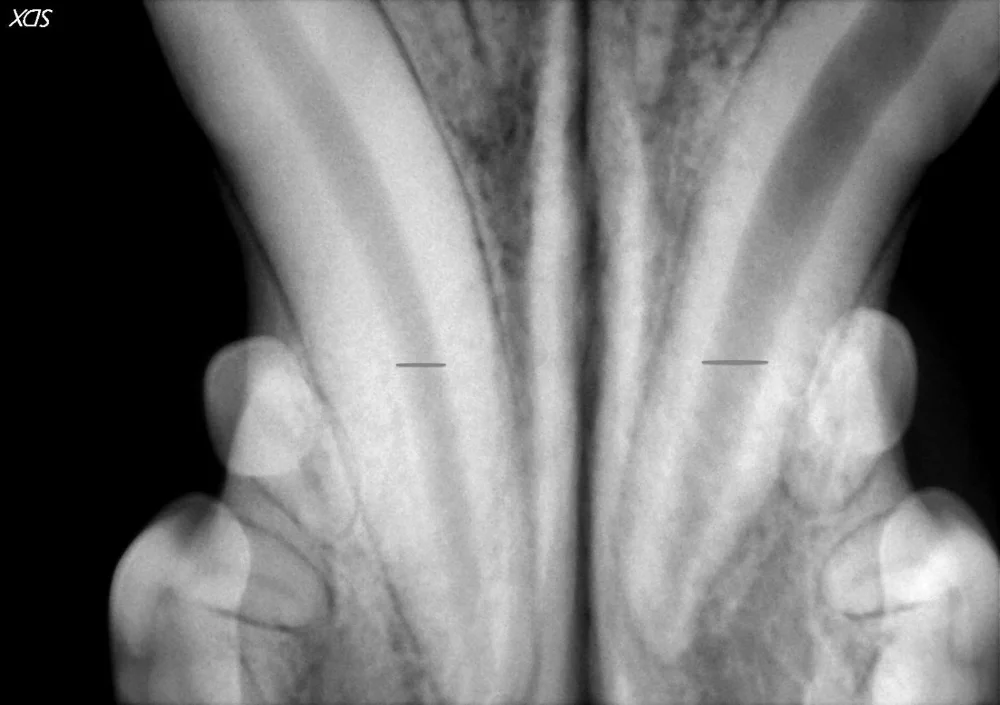

A dog’s lower canine teeth are imaged in this dental x-ray. They both appeared normal on examination. On x-rays inner pulp canal of the tooth is seen as the dark central part running along the tooth. When comparing the two large canine teeth, the widths of the pulp canals should be the same. However, the widths of the teeth, highlighted by the lines on the radiographs, are quite different. The canine tooth on the right has a much wider canal which indicates tooth death in this case. This tooth should be treated with root canal therapy or extraction.